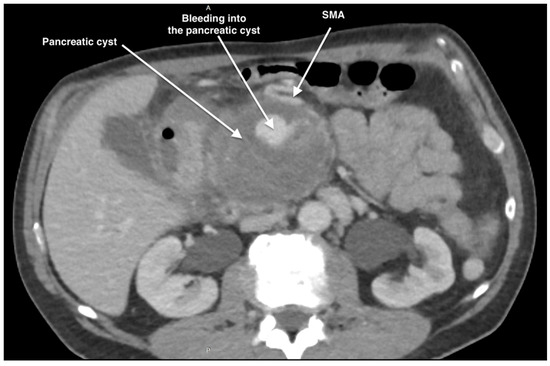

Management of a Rare Case of Superior Mesenteric Artery Aneurysm Associated with a Pancreatic Cyst Complicated by Acute Rupture: A Case Report and Review of Literature

2. Case Report